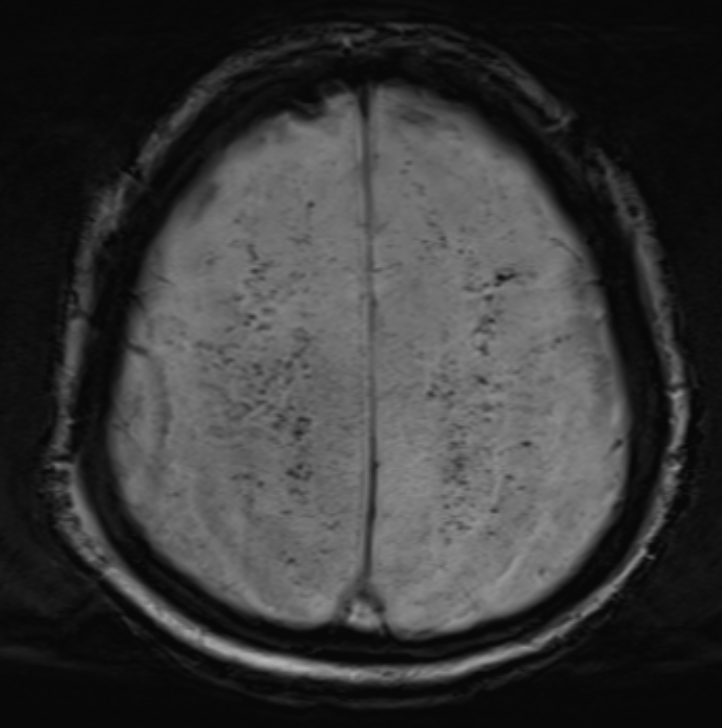

4.주요 MRI 소견

1) Starfield pattern (별자리 패턴)

· DWI에서 고강도 신호가 다발성으 나타남.

· 미세색전이 뇌의 회백질(gray matter) 과 백질(white matter) 에 광범위하게 분포.

· 해당 패턴은 CFE의 대표적인 소견이며, 매우 특징적인 영상 소견!